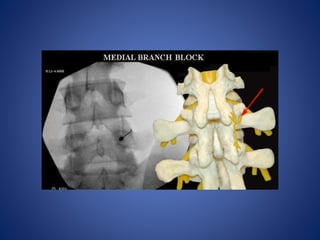

Facet joint injection and/or facet nerve block

(e.g. medial branch block) is proven and

medically necessary when used to localize

the source of pain to the facet joint

Diagnostic Facet JointInjections Facet joint injection and/or facet nerve block (e.g. medial branch block) is proven and medically necessary when used to localize the source of pain to the facet joint